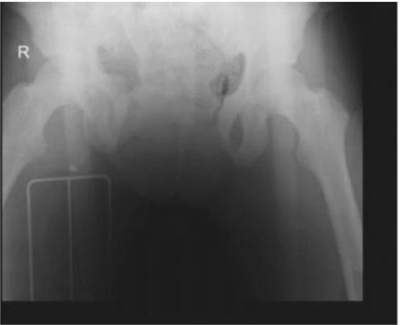

Mulher de 33 anos de idade foi atropelada por automóvel, há 30 minutos. Ela foi atendida no local do acidente pela equipe avançada do resgate. No início do atendimento no local do acidente, a paciente estava inconsciente, com pressão arterial = 80 x 50 mmHg; frequência cardíaca = 110 bpm. Naquele momento, foi realizada a intubação orotraqueal e administrado 1 litro de cristaloide em acesso venoso periférico. O resgate trouxe a paciente ao pronto-socorro de um hospital terciário. Foi admitida no pronto-socorro com pressão arterial inaudível e frequência cardíaca = 140 bpm. Na sala de emergência, foram realizados FAST e radiografia de tórax, que resultaram normais, e a radiografia de bacia que está exibida abaixo. Após a reposição de hemoderivados e fechamento da bacia com lençol, qual é a sequência de condutas adequada ao caso?